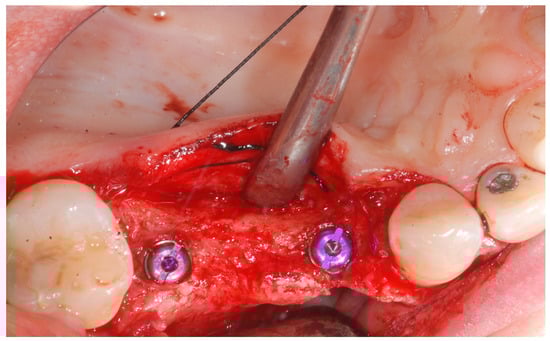

Local anesthesia was obtained with mepivacaine 20 mg/mL with epinephrine 1:100.000 (Optocain, Molteni Dental, Milan, Italy) injections. To raise a mucoperiosteal flap, a crestal incision followed by oblique releasing incisions were made to allow for a wide flap basis as well as sufficient access to the defective ridge area. The flaps were carefully raised using tissue elevators. The bone ridge was examined and any soft tissues remaining on the crest were meticulously removed with a surgical curette (Figure 2).

Figure 2. Trapezoidal flap elevation and initial bone thickness.